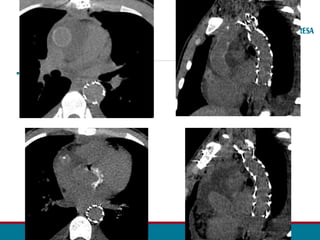

•FOTOS ANGIO TC POS OP

ANGIOTOMOGRAFIA DA AORTA TOTAL 11/06:

• Achados pós-operatórios de correção de coarctação de aorta (dado clínico), havendo próteses

valvar aórtica e na aorta ascendente, patentes. Há ainda endoprótese aórtica, também

pérvia, com ancoragem proximal na região da emergência da artéria carótida esquerda,

estendendo-se até o terço médio torácico descendente. Não há evidências de endoleak.

• Fios de esternorrafia bem posicionados.

• Pequena coleção hipoatenuante alongada retrosternal, com focos gasosos em permeio,

apresentando volume grosseiramente calculado em 23 cm³.

•Associa-se pequeno / moderado pneumomediastino, além de pequeno pneumoperitônio.

•Pequeno derrame pericárdico.

•Pequeno derrame pleural bilateral hipoatenuante.

•As demais porções da aorta torácica descendente apresenta diâmetro usual.

•Houve redução da dilatação de artérias intercostais e torácicas internas, na comparação com

estudo tomográfico prévio do dia 28/05/2019 (exame pré-operatório).

•Artérias ilíacas comuns, internas e externas estão patentes.

Obs.: Como achados de exame não direcionado, verificamos: Pequena ascite.